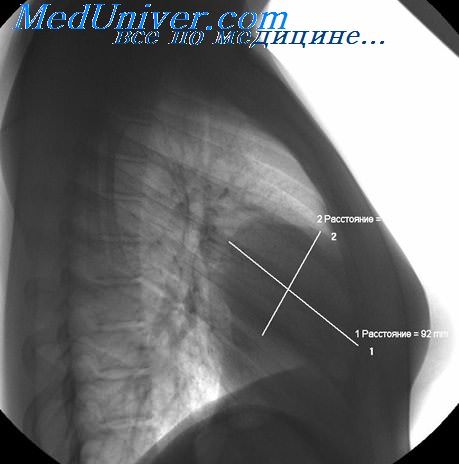

Рентгеновские снимки тератомы средостения: Диагностика и лечение

Раздел: Фотоэссе